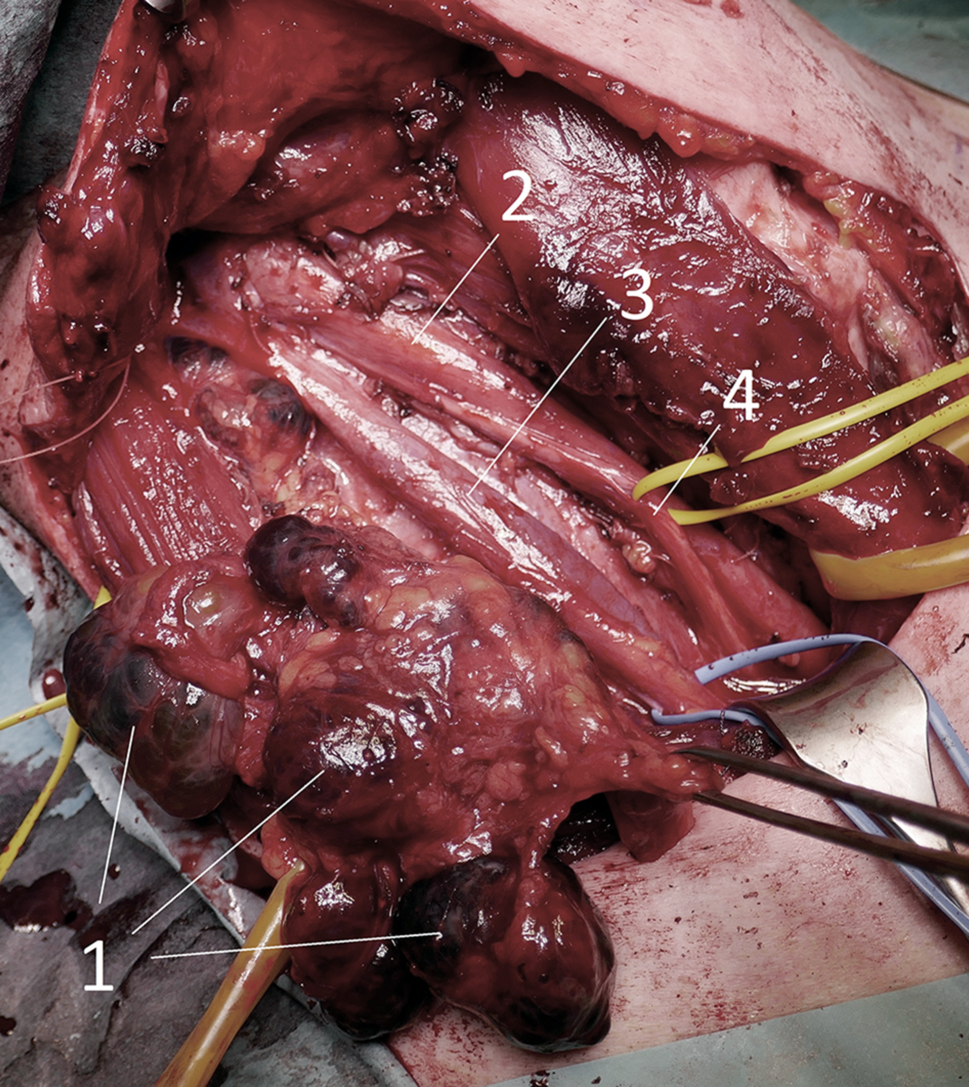

Abb. 5

Laterale Halsdissektion (Level II–V) bei ausgedehntem Lymphknotenbefund: 1 = Lymphknotenmetastasen, 2 = A.carotis, 3 = V.jugularis, 4 = N.Vagus

Die Ultraschalldiagnostik für Schilddrüse, Lymphknoten und Nebenschilddrüsen sollte demnach idealerweise auch vom Chirurgen beherrscht werden. Ein positiver Lymphknotennachweis im lateralen Kompartment (Regio IV, V, III, II – einen Überblick zeigt das CT in Abb. 4) lässt dann schon präoperativ eine laterale Halsdissektion einplanen (OP Bild Abb. 5), was sowohl für den Zugangsweg, die geplante Länge der Operation und auch die Wahl des spezialisierten Chirurgen von wesentlicher Bedeutung ist. Schwierig ist speziell die sonographische Lymphknotendiagnostik im zentralen Kompartment (Regio VI) bzw. im oberen mediastinalen Kompartment (Regio VII), die bei routinemäßiger Ultraschalluntersuchung durch Radiologen und Nuklearmediziner nicht immer erfasst wird. Anzumerken ist auch, dass retrotracheale, paraösophageale und vor allem sogenannte retrorecurrente (dorsal des N. laryngeus recurrens) Lymphknoten oft mit der Sonographie nicht einsehbar sind (Abb. 6; [1517]).